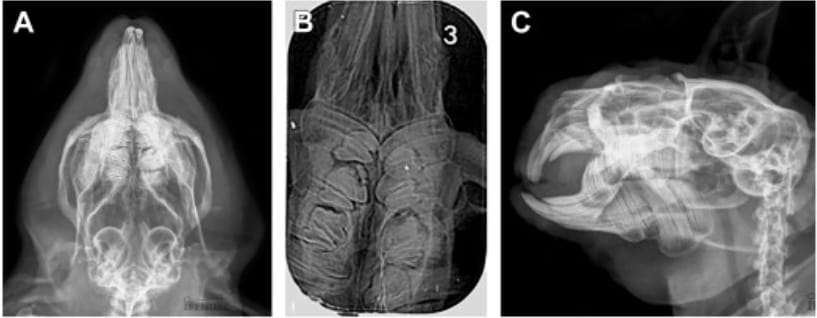

Radiography of a guinea pig with macrodont teeth (A–C). (A) Isolated view of a maxilla according to Bohmer.8 A homogeneous structural alteration is visible in the mesial part of the right maxillary M2, leading to an enlarged crown outline. The mesial periodontal space is widened secondary to crown substance loss. The left maxillary M2 also displays features of macrodontia. Crown margins are uneven, pulp cavities are not visible, and both mesial and distal periodontal spaces are significantly widened. The left maxillary M3 is clearly displaced caudally and rotated due to the enlarged M2 crown outline. (B) Dorsoventral intraoral projection of the maxilla. Homogeneous structural changes are visible in the mesial parts of the right maxillary M1 and M2. Crown outlines are enlarged, with uneven mesial edges and a minor defect contributing to periodontal space widening. Similar changes are seen in the mesial parts of left M2 and M3. Loss of dental substance in the mesial portion of M2 leads to periodontal space widening. (C) Latero-oblique projection of the right mandible. Marked crown enlargement of M2 with blurred structural boundaries. The mesial pulp cavity shows increased radiodensity. Periodontal spaces are widened, and a longitudinal radiolucent line running through the crown suggests a possible fracture. Periapical features of periosteal reaction are visible. The M1 and M3 crowns show secondary rotation, giving the impression of reduced tooth size.